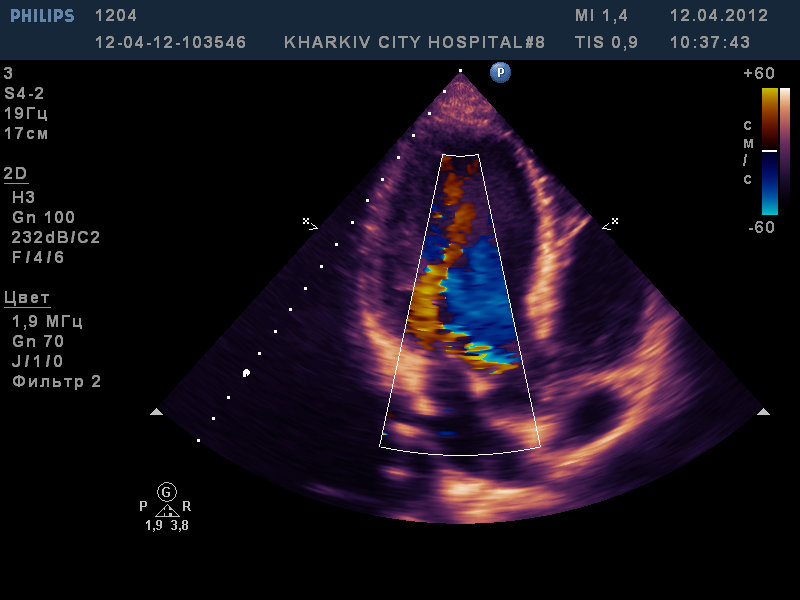

Парень 22 лет/

двухстворчатый аортальный клапан с выраженной аортальной недостаточностью, расширение восходящего отдела аорты до 4,2см, пролабирование передней створки МК III степени с незначительной регургитацией, дилатация левых полостей (КДР 6,6 КСР 4,5 ЛП 4,2), гипертрофия левого желудочка.

На видео видно двухстворчатый аортальный клапан с неполным смыканием створки с выраженной регургитацией (высокоскоростная струя под углом ударяет в переднюю створку митрального клапана вызывая пролабирование).